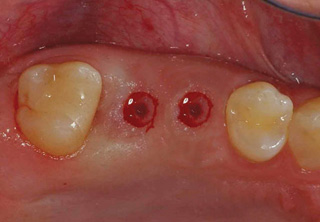

청담네오플란트 원데이 임플란트

하루만에 발치와 임플란트 식립을 동시에!

일반적으로 살릴 수 없는 치아를 발치하면, 2~3개월의 잇몸뼈 회복기를 거친 후 임플란트를 식립하게 됩니다. 하지만 잇몸뼈의 소실이

심하지 않은 경우 임플란트의 전체 치료기간 단축과 환자분의 불편감을 최소화하기 위해 내원 당일 발치 및 임플란트 식립을 진행할 수 있습니다.

필요에 따라 치조골 이식이 필요할 수 있으며, 가능한 경우 당일 임시 보철물 장착까지 해드려 심미적 기능을 회복할 수 있습니다.

발치 후 임플란트를 식립하고, 바로 임시 보철물을 제작함으로써 일상생활에서 불편감을 최소화할 수 있습니다.